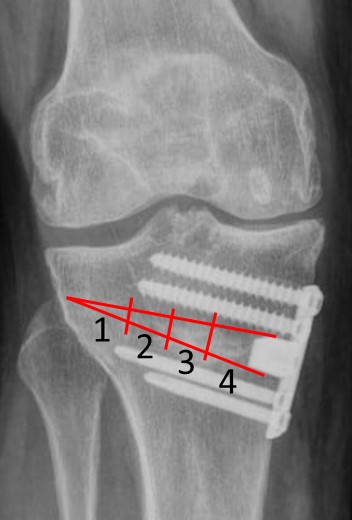

La consolidación ósea radiológica se determinó mediante un examen postoperatorio con radiografías anteroposteriores de la rodilla, utilizando la versión del índice de llenado de osteotomía de Brosset y cols19. En una radiografía anteroposterior de rodilla, el espacio de la osteotomía se dividió en cuatro zonas, desde la cortical lateral (zona 1) hacia la cortical medial (zona 4) (Fig. 7). La unión ósea radiológica se definió cuando el callo óseo alcanzó la zona 3, es decir, cuando al menos el 50 %, o una mayor parte del espacio total de la brecha de la osteotomía, se cubrió con la formación del callo. Para una visibilidad completa del espacio de la osteotomía, se recomienda una inclinación cefálica de 10° del tubo de rayos X.

Figura 7. Evaluación de la consolidación ósea según los conceptos de Brosset y cols. Se divide la brecha de la osteotomía en cuatro zonas (enumeradas desde lateral hacia medial)